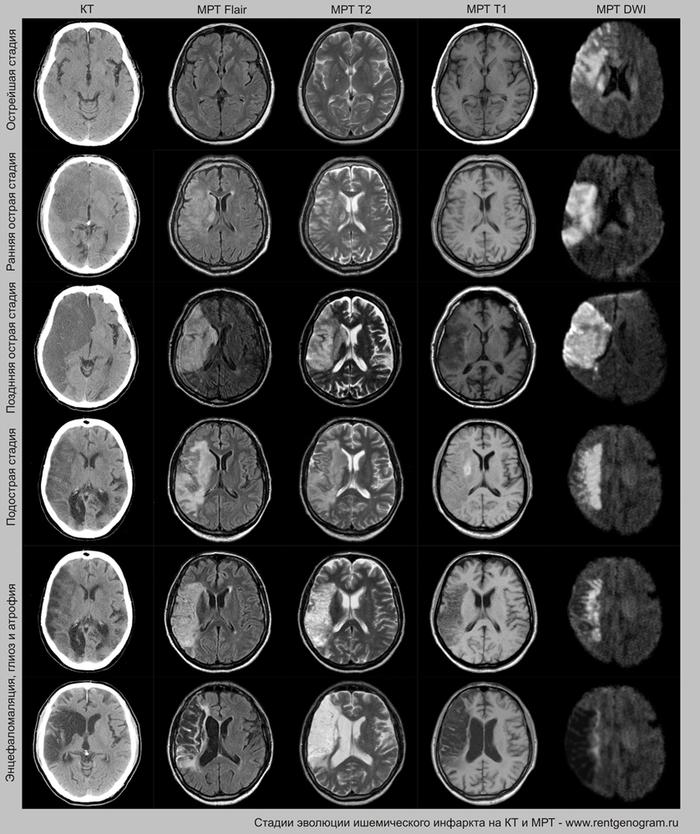

Этапы ишемического инфаркта

- острая фаза (первые 6 часов – возможны вмешательства)

- острое течение (с 6 до 24 часов – инфаркт виден на КТ и МРТ)

- подострая фаза (с 24 часов до 6 недель – накопление контрастного вещества)

- хроническая стадия (резорбция и рубцевание – после 6 недель)

Острая фаза (первые 6 часов)

На МРТ и КТ изменения могут отсутствовать. На МРТ у некоторых пациентов могут быть первые признаки ишемии. На DWI область ишемического повреждения может быть видна через 2,5 часа после появления первых симптомов.

С 4-5 часов на DWI должны быть заметны признаки ишемического поражения, которые представляют собой «ядро» инфаркта.

Диагностика ишемического инсульта: КТ и МРТ

На остром этапе (Т2, Т1 и Flair могут сохранять нормальные результаты), на МРА можно обнаружить окклюзию артерии (при атеротромбоэмболическом и кардиоэмболическом механизмах), что будет выглядеть как отсутствие МР-сигнала от ведущей артерии (ВСА или СМА). Контрастное усиление на МРТ в остром этапе не приводит к накоплению контраста в области повреждения.

Острая фаза (6 — 24 часа)

В течение острого этапа на МРТ и КТ выявляются все морфологические признаки ишемического инсульта. Область острого ишемического инфаркта визуализируется как зона ↑Т2, ↑Flair, ↑DWI и ↓Т1 ↓ADC. Можно обнаружить тромб в артерии. На КТ в остром этапе также чётко дифференцируется поражённая область, представляющая собой участок с потерей дифференциации мозговых структур и снижением их плотности. Контрастирование в остром периоде не показывает патологических участков с накоплением контраста.

Подострая фаза (24 часа — 6 недель)

На подостром этапе происходит разрушение гематоэнцефалического барьера, что приводит к вазогенному отеку, увеличивая объем ишемического инфаркта, возникновение масс-эффекта и возможного вклинения в случае обширного поражения (например, вклинение поясной извилины под фалькс или миндалин мозжечка в большое затылочное отверстие).

Разрушение гематоэнцефалического барьера (ГЭБ) приводит к накоплению контрастного вещества в области ишемического инсульта, используя технику контрастирования по «гиральному типу».

Когда в мозговых артериях происходит реканализация кровотока, это может привести к образованию геморрагических пропитываний и кровоизлияний («красный компонент» ишемического инфаркта), что будет отображаться на МРТ как ↑ на Т1 и Т2*, а на КТ — как участки с гетерогенной повышенной плотностью. На более поздних этапах подострой стадии наблюдается нормализация ранее повышенных показателей DWI и ADC, известная как «псевдонормализация» диффузии.

Хроническая фаза (более 6 недель)

В хроническом периоде наблюдаются процессы репарации и пролиферации, что ведет к обратному развитию вазогенного отека и восстановлению ГЭБ, что проявляется полным отсутствием контрастного усиления в зоне поражения. В местах энцефаломаляции формируются ликворные кисты (лакунарный инсульт) или происходят кистозно-глиозные изменения. Также фиксируется снижение кровотока или полная окклюзия артерии в области инфаркта.

Может начать происходить гибель аксонов нейронов, входящих в пирамидный тракт (дегенерация Тюрка-Валлера), создавая выраженную зону глиоза, которая повторяет ход пирамидного тракта. Высокий МР-сигнал на DWI полностью исчезает. Зона кистозно-глиозных изменений может приводить к тракционной дилатации полостей, что вызывает асимметричное растяжение желудка, прилегающего к зоне глиоза (гидроцефалия ex-vacuo).

Сравнительный анализ ишемического инфаркта на КТ и МРТ